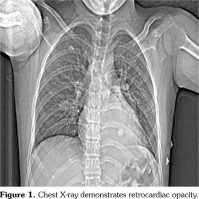

Pathergy test was performed due to the presence of recurrent oral and genital ulcers, supporting the diagnosis of BD. Pathergy test was positive and he was diagnosed as BD according to the history, physical examination and laboratory findings. Monthly intravenous cyclophosphamide pulses combined with high dose methyl-prednisone were initiated and followed by prednisolone 2 mg/kg/day. Afterwards, left lower lobectomy was performed. Pathological examination revealed PAA with thrombus in the lumen, fibrosis and lymphoplasmacytic inflammatory cell infiltration adjacent to small- and medium- sized vessels (Figure 3). He was clinically well after lobectomy and admitted for the second pulse immunosuppressive therapy. Meanwhile, CT angiography was performed to evaluate the aneurysm at the right lower lobe which showed regression of PAA from 16 mm to 6 mm in diameter. Endovascular embolization was planned for the right lower lobe PAA. However, unfortunately, he presented with massive hemoptysis five days later. The patient passed away with massive hemoptysis originating from the right lower lobe PAA.